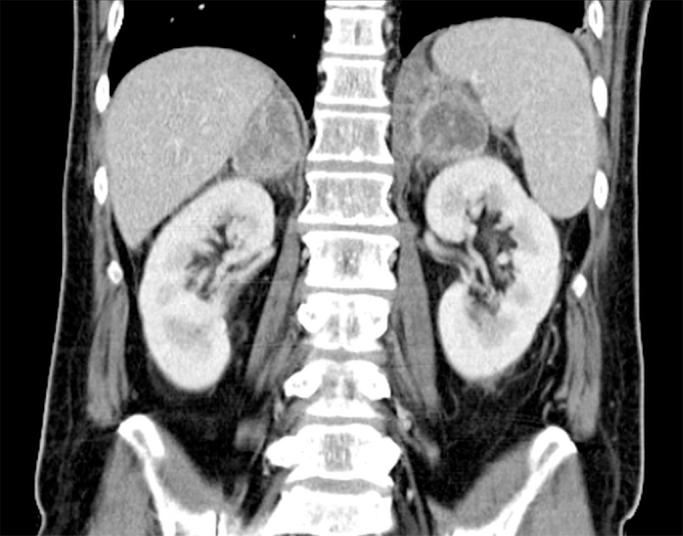

Paracoccidioidomycosis is a systemic fungal infection caused by and endemic in certain areas of Central and South America. We report a case of a 62-year-old-man with a complex history of tuberculosis and imaging findings of a cerebral lesion and bilateral adrenal enlargement. Biopsy of adrenal gland revealed . This case highlights the importance of travel history for diagnosis of paracoccidioidomycosis in non-endemic areas and emphasizes the clinical and histopathological similarities with tuberculosis.

副球孢子菌病是一种由[未提及具体病因]引起的系统性真菌感染,在中美洲和南美洲的某些地区流行。我们报告一例62岁男性病例,该患者有复杂的结核病病史,脑部病变及双侧肾上腺增大的影像学表现。肾上腺活检显示[未提及活检结果]。该病例强调了旅行史在非流行地区诊断副球孢子菌病中的重要性,并强调了其与结核病在临床和组织病理学上的相似性。